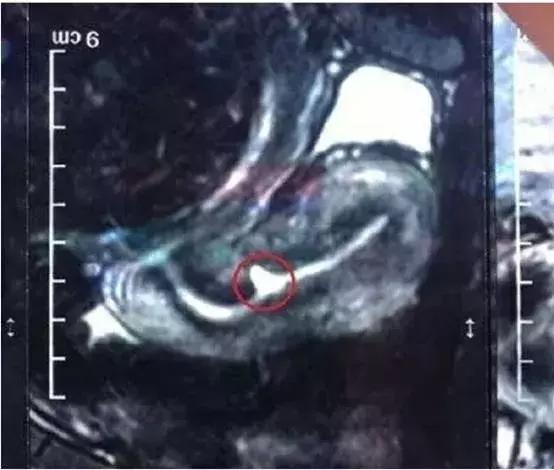

5. 腹腔镜、阴式手术

无论什么样的治疗方案,结合患者自身的情况,是否有再生育的要求等综合判断,消除憩室、恢复正常的组织结构,减少憩室内物质的聚集和生成,使经血及分泌物顺利流出为目的。采用外科手术治疗需要结合磁共振检查充分评估切口的大小、部位、与膀胱的关系等,力争找到创伤最小、治疗效果最佳的途径。